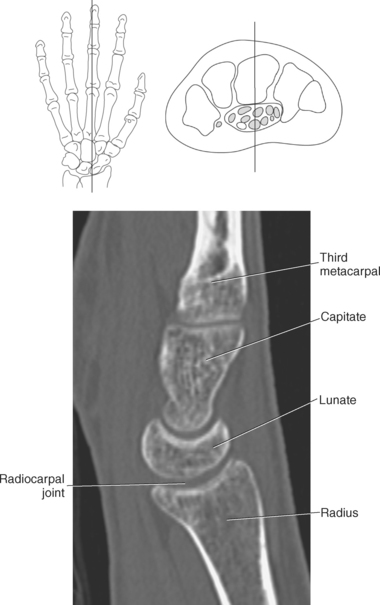

The bony anatomy of the wrist and hand consists of the distal radius and ulna, 8 carpal bones, 5 metacarpals, and 14 phalanges (Figure 9.101). Both the distal radius and ulna have a conical styloid process that acts as an attachment site for ligaments. The radial styloid process is located on the lateral surface of the radius, whereas the ulnar styloid process is located on the posteromedial side of the ulna. The carpal bones are arranged in proximal and distal rows. Located in the proximal row of carpal bones are the scaphoid (navicular), lunate (semilunar), triquetral (triquetrum), and pisiform bones. The pisiform is considered a sesamoid bone that is embedded in the tendon of the flexor carpi ulnaris. The distal row consists of the trapezium (greater multangular), trapezoid (lesser multangular), capitate (os magnum), and hamate (unciform) bones (Figures 9.102 through 9.114). The five metacarpals are small tubular bones with a proximal end (base), distal end (head), and shaft (body). The 14 phalanges that make up the fingers are short tubular bones. Like the metacarpals, each phalanx consists of a proximal (base), middle (body or diaphysis), and distal (head) portion. Each digit consists of 3 phalanges (proximal, middle, and distal), except for the thumb (first digit), which has only 2 phalanges (proximal and distal). The articulation of the phalanges of the second through fifth digits creates three interphalangeal joints: the metacarpophalangeal (MCP) joints classified as condyloid joints, proximal interphalangeal (PIP), and distal interphalangeal (DIP). The proximal and distal interphalangeal joints are classified as hinge joints (Figure 9.101). The first digit, which consists of 2 phalanges, has just two joints: the MCP joint, classified as a saddle joint, and an interphalangeal joint, classified as a hinge joint (Figure 9.101).

The joints of the wrist and hand are quite complex and consist of the following: distal radioulnar articulation, radiocarpal articulation (proximal joint of hand), midcarpal articulation (distal joint of hand), intercarpal articulations (articulations between proximal and distal carpals), carpometacarpal articulations (between carpals and metacarpals), the intermetacarpal articulations (between bases of metacarpals two through five) and the interphalangeal joints (between phalanges of each digit) (Figures 9.111 and 9.115). The distal radioulnar articulation, also called the distal radioulnar joint (DRUJ), is created when the ulnar notch of the radius moves around the articular circumference of the ulna, providing the movements of supination and pronation. The main stabilizing element of the DRUJ is an articular disk called the triangular fibrocartilage complex (TFCC). The TFCC is a fan-shaped band of fibrous tissue that originates on the medial surface of the distal radius and traverses horizontally to insert on the ulnar styloid process (Figures 9.115 and 9.116). It rotates against the distal surface of the ulnar head during pronation and supination and separates the ulna from the carpal bones. The proximal surface of the radiocarpal articulation is formed by the articular carpal surface of the radius and the TFCC, whereas the distal surface is formed by the articular surfaces of the scaphoid, lunate, and triquetrum and the interosseous ligaments connecting them (Figures 9.111 through 9.115). The midcarpal joint is formed by the articulations between the proximal and distal carpal rows (Figures 9.110 and 9.115). The articulation between the carpals within each row creates the intercarpal joints (Figures 9.111 and 9.115). The carpometacarpal joints are formed by the articulations between the carpus and the five metacarpals (Figure 9.111 and 9.115). The carpometacarpal joint of the thumb is an independent joint formed by the articular surfaces of the trapezium and first metacarpal, creating a pure saddle joint. The carpometacarpal articulations of the two to five digits are amphiarthrotic joints with little mobility (Figures 9.105 and 9.115). The intermetacarpal articulation exists between the base of the metacarpals and is joined by the palmar and dorsal metacarpal ligaments (Figure 9.115).